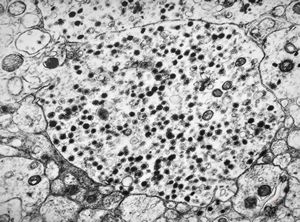

F, 68y. | APUD carcinoma mammae